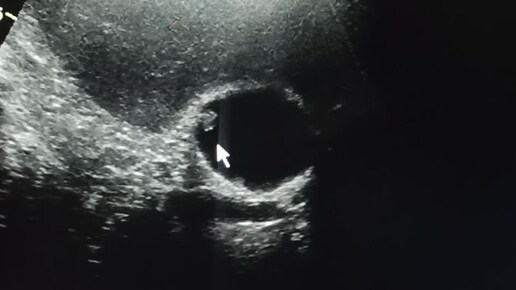

Начинающим врачам УЗИ: полипы стенки желчного пузыря.